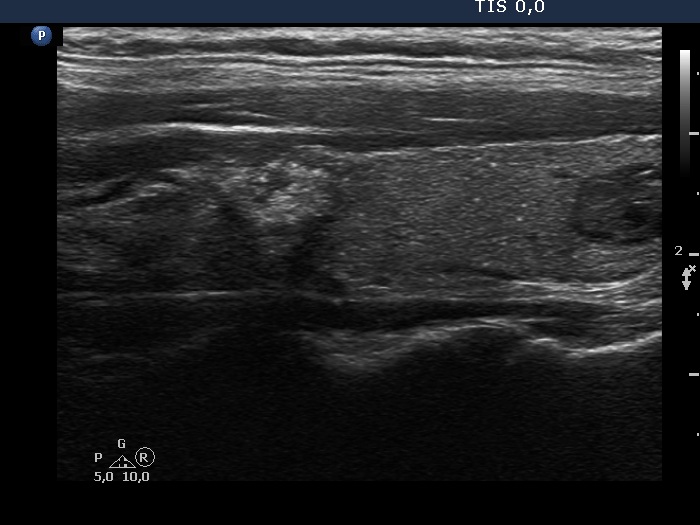

100 consecutive cases of papillary cancer - case 080 (ultrasonographic picture 6)

Left lobe, another longitudinal scan. Note the bright echogenic foci (microcalcifications) betweeen the two nodules.